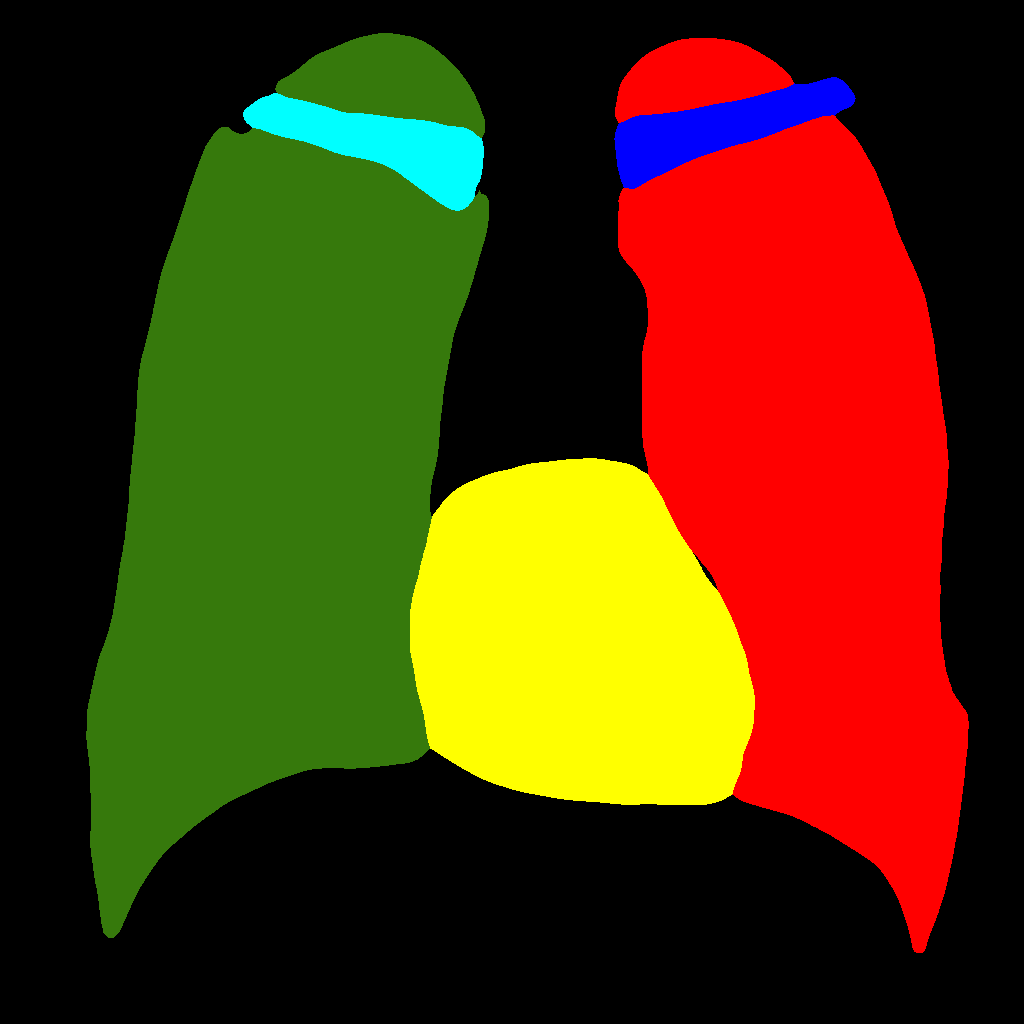

In this approach, the generation procedure is divided into two steps. The first one consists in generating the labels through a PGGAN, while, in the second, the translation from the label to the corresponding chest X–ray image is carried out, using Pix2PixHD (see Figure 2).

Figure 5 and Figure 6 display some examples — randomly chosen from all the generated images — of the label–maps and the corresponding chest X–ray images generated with the three methods described in Section 3, using the FULL_DATASET and the TINY_DATASET, respectively. We can observe that, with the single and two–stage methods, the images tend to be more similar to those belonging to the training set. For example, in most of the generated images there are white rectangles, which resemble those present in the training images, used to cover the names of both the patient and the hospital. Instead, the three–stage method does not produce such artifacts, suggesting that it is less prone to overfitting.